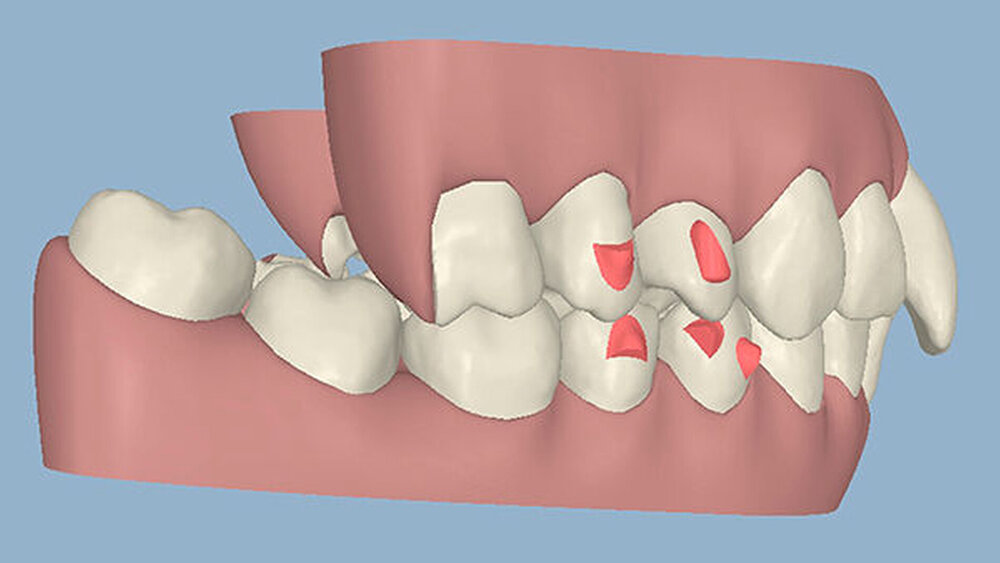

Die Sulkustiefen konnten auf etwas weniger als 4 mm reduziert werden, während der Blutungs- und Plaque-Index bei weniger als 15 Prozent lag. Daher wurde eine kieferorthopädische Behandlung über die nächsten zwei Jahre in Kombination mit engen zahnärztlichen Kontrollen geplant. Als Mittel der Wahl entschieden wir uns gemeinsam mit dem Patienten für das Invisalign-System, da hiermit sowohl eine Schienung als auch eine kraft-arme Bewegung der Zähne möglich sein sollte. Für den Frontzahnbereich wurden keine Attachments geplant, so dass hier eine unnötige Hebelwirkung umgangen werden konnte (Abbildung 3).

Um einen kompletten Lückenschluss im Oberkiefer zu ermöglichen, musste im Unterkieferfrontzahnbereich zusätzlich zur Derotation und Positionierung der Zähne - insbesondere Zahn 41 - von approximaler Schmelzreduktion, kurz ASR , Gebrauch gemacht werden, um einer Tonn`schen Diskrepanz entgegenzuwirken (Abbildung 4).